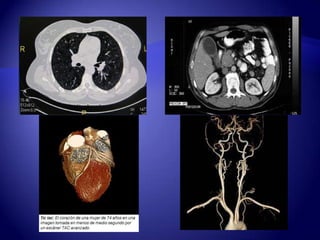

 El ingenieroGodfrey Houndsfield y el físico Allan Mcleod Cormack explicaron el principio de laTC en 1968. Expuso que el principio básico consistía en una exposición de un haz de rayos “X” en sentido axial al paciente. Que era registrado por un detector colocado más allá del paciente, repitiendo en múltiples ángulos de la circunferencia.

 En 1972en el hospital Morley de Inglaterra se instaló el primer tomógrafo computado comercial.

 Procedimiento dediagnóstico a través de imágenes que utiliza una combinación de radiografías y tecnología computada para obtener imágenes de cortes transversales (axiales) del cuerpo.

 Muestra imágenesdetalladas de cualquier parte del cuerpo:  Huesos  Músculos  Grasa  Órganos  Vasos sanguíneos

TC de alta resolución TC helicoidalo espiral TC ultrarápida Angiografía porTC TIPOS DE TAC